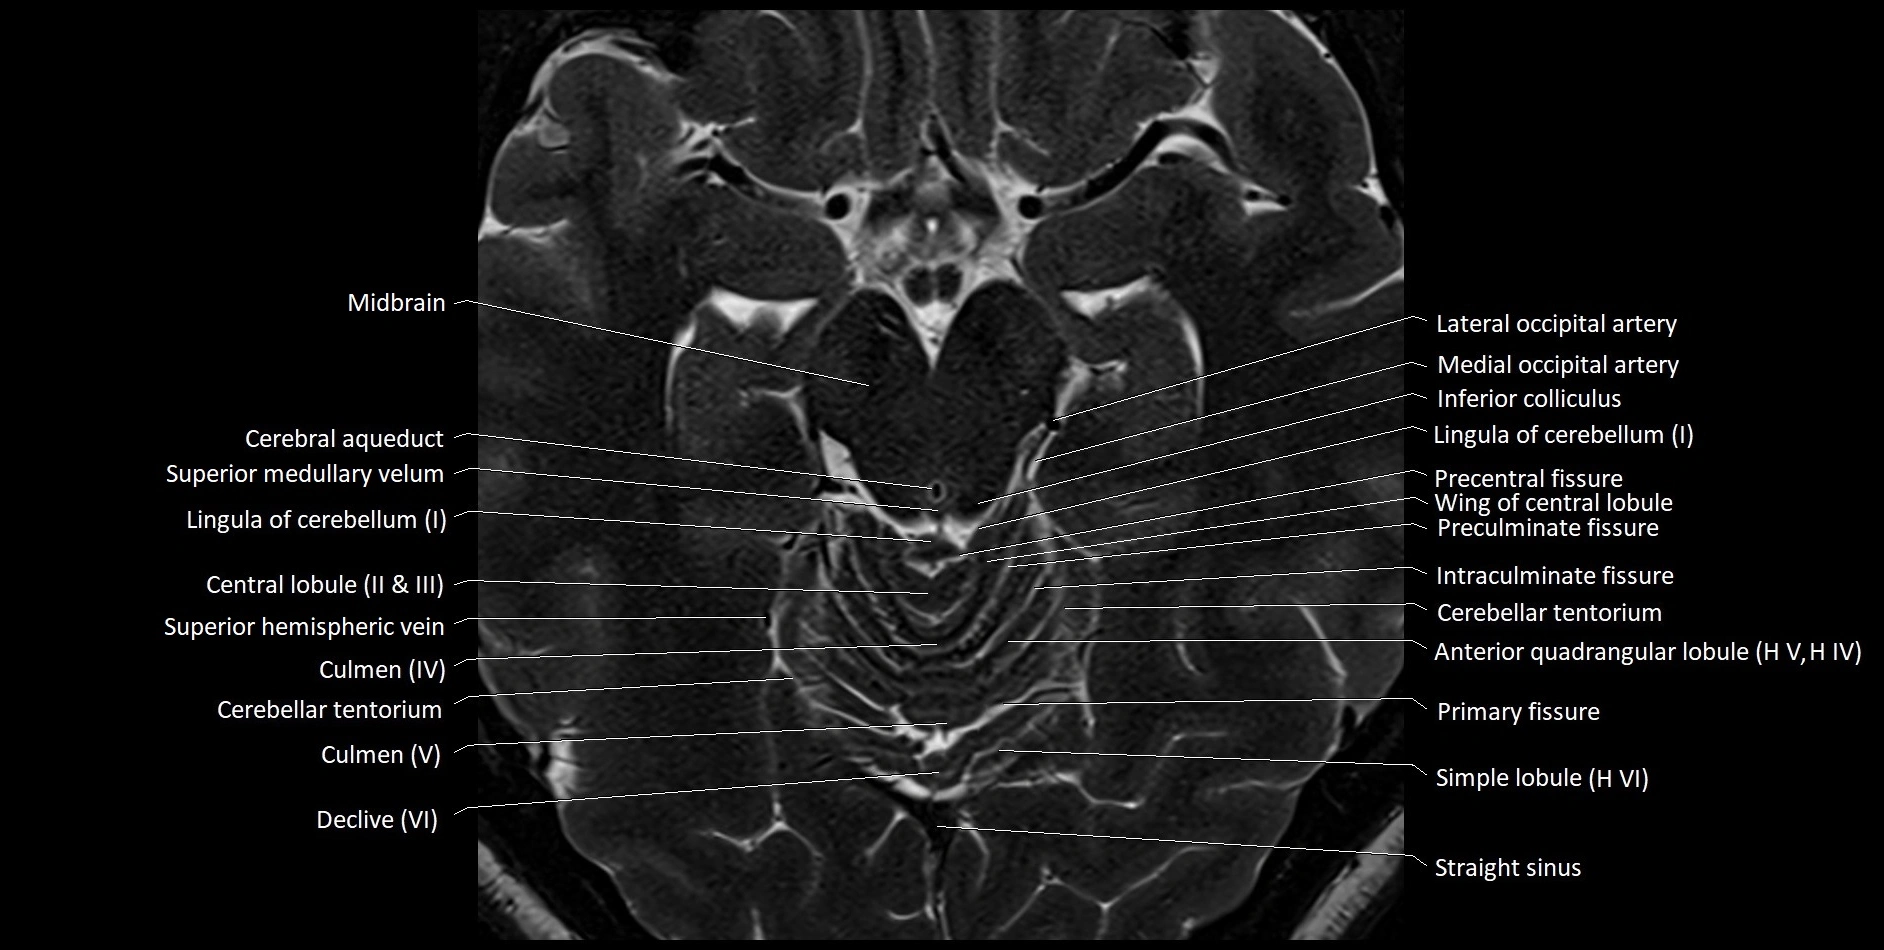

MRI images